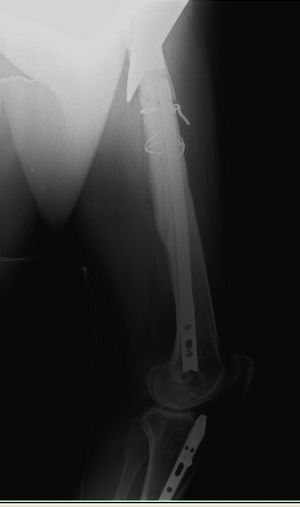

Хочется услышать ваше мнение. Пациентка 48 лет, без вредных привычек,

получила свежую травму (с\3 диафиза правого бедра) при падении с лестницы.

Ранее (8 лет назад) была множественная травма, на бедре–  перелом с\3,

выполнен остеосинтез DFN  Synthes (в др. ЛПУ). Перелом диафиза

консолидировался очень медленно, от реостеосинтеза категорически

отказывалась, в результате к 2 годам наступило сращение. Беспокоили боли

при нагрузке, на рентгенограммах–  зона разрежения вокруг кончика

(проксимального) стержня и проксимальных винтов, согласилась лишь на

удаление дистальных винтов для динамизации стержня. Пациентка пропала из

поля зрения. Затем спустя 2 года при падении получает чрезвертельный

перелом, выполнен остеосинтез бедренным винтом ( DHS ).

Планирую удаление имплантов (кроме проволоки), рассверливание

костно-мозгового канала (сейчас стоит гвоздь 10 мм, попытаюсь

рассверлить до 14-15 диаметра, чтобы поставить 12 мм или 13 мм гвоздь),

внутрикостный остеосинтез блокированным стержнем (динамически).

1.Так как нет оригинального инструмента  Synthes , то интересует резьба

на конце стержня какой диаметр и метрическая ли она.

2.Есть ли заглушка на стержне (мне так кажется, что нет).

3.Нужно ли заполнять полость аутокостью от шеечного винта.